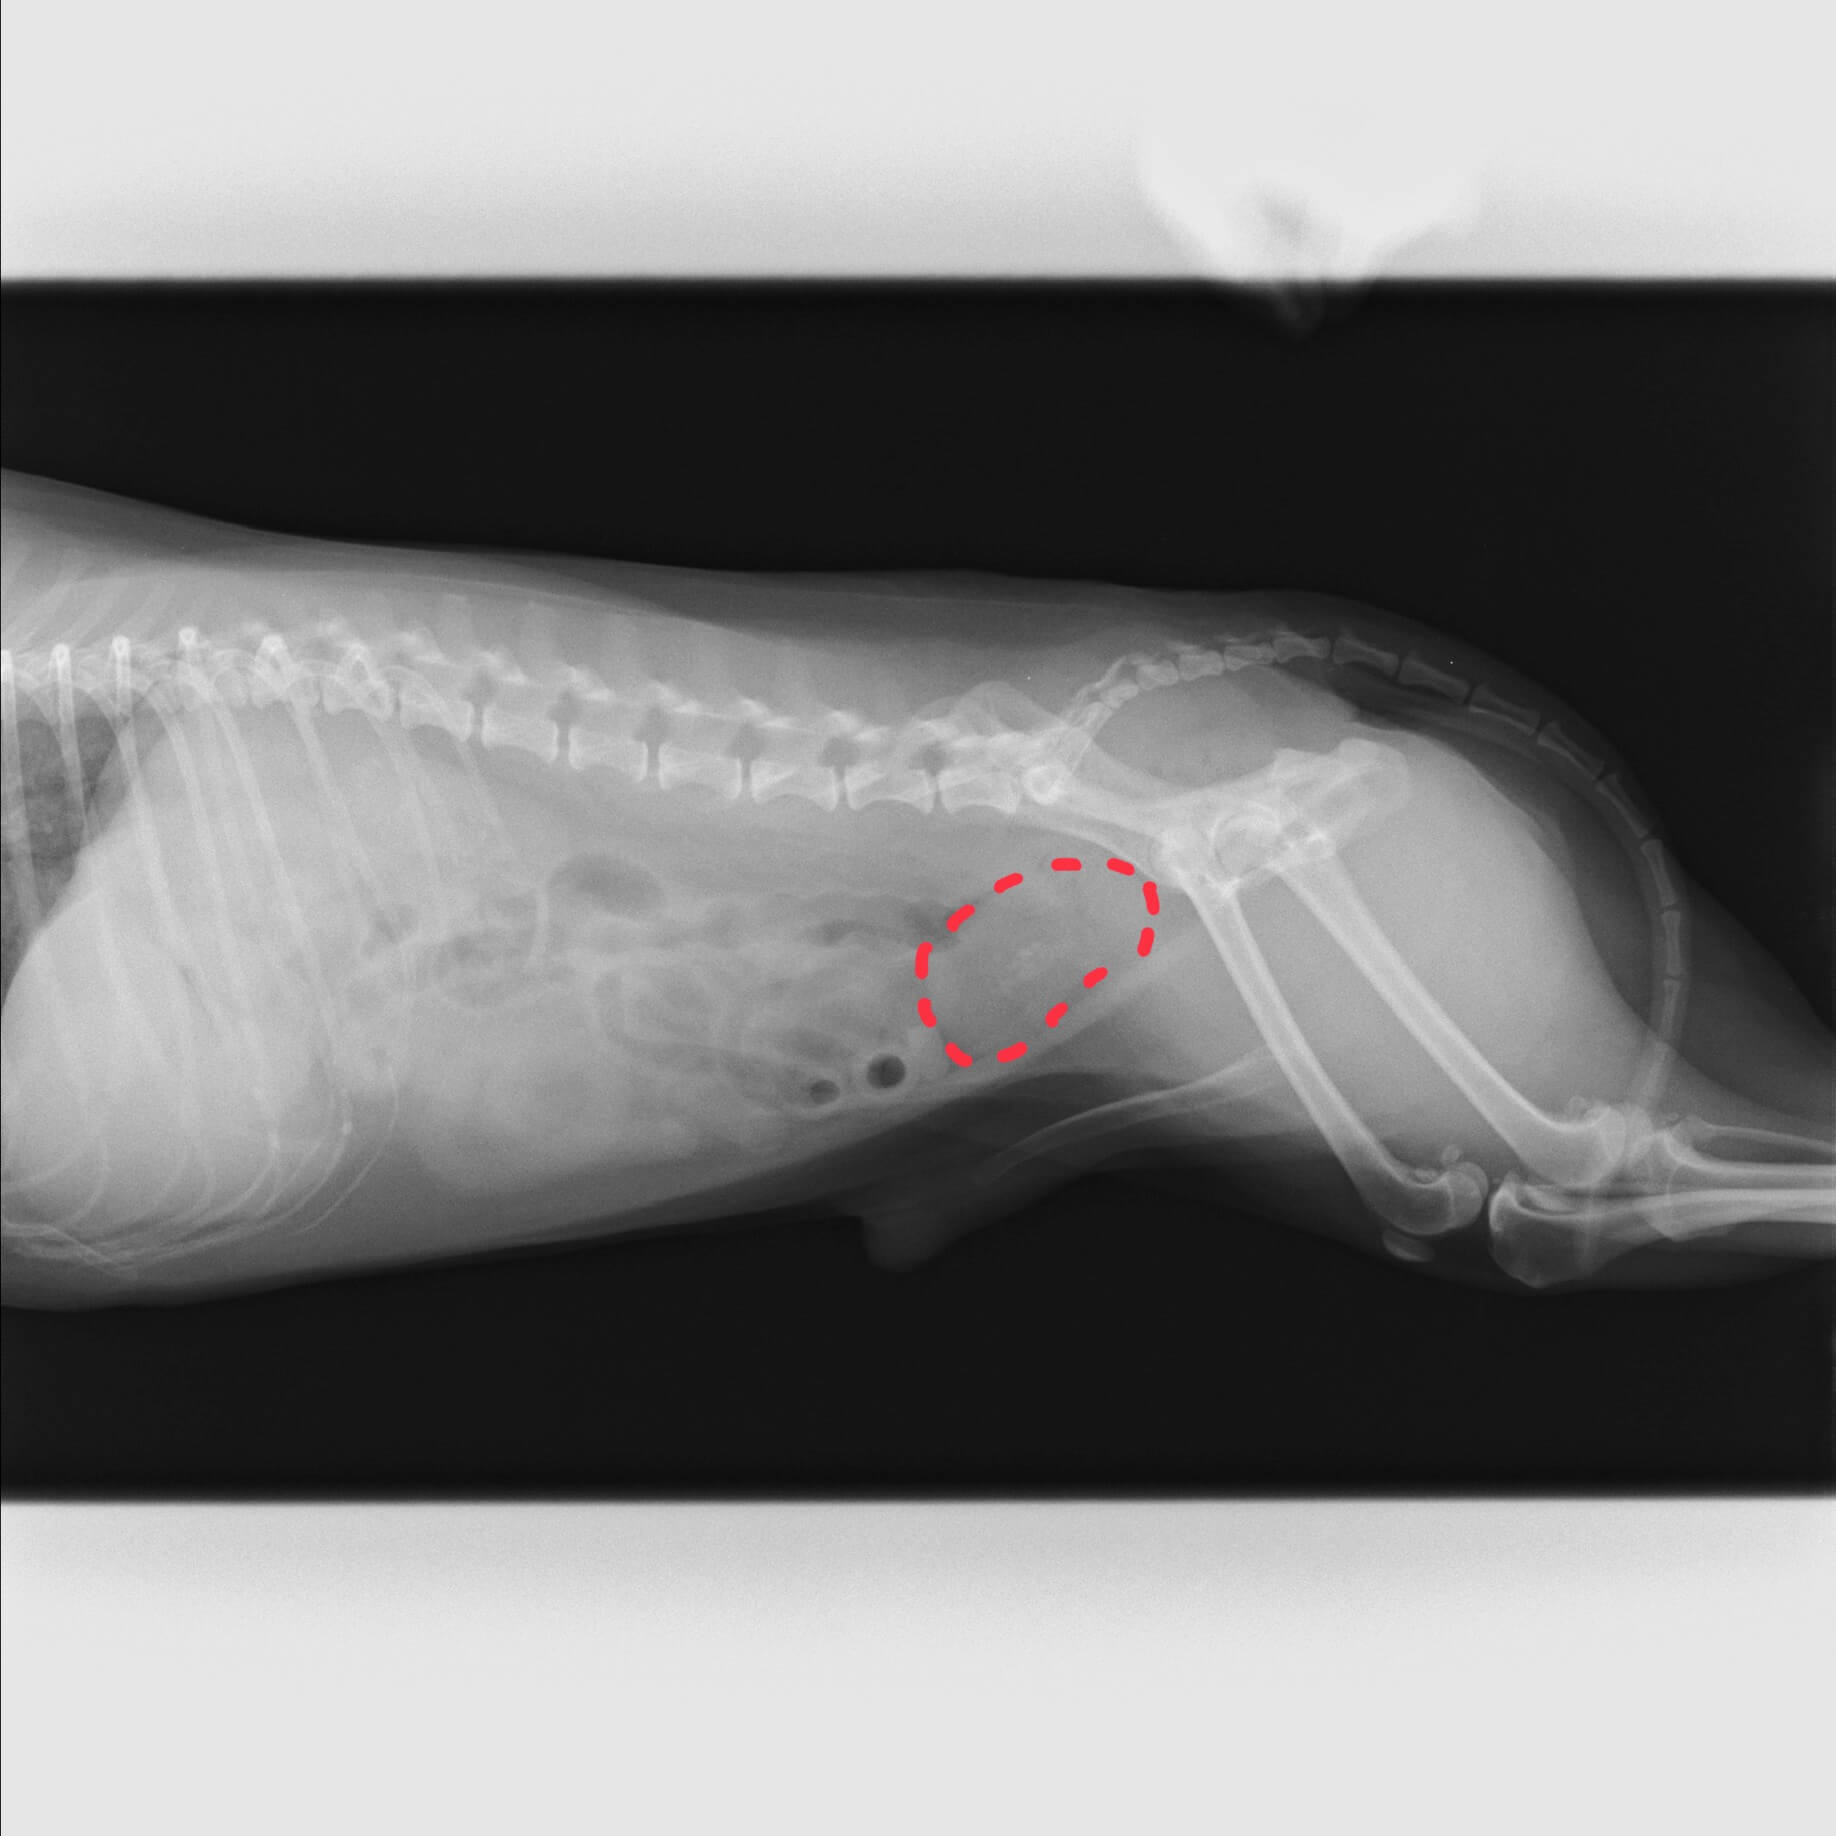

手術前のレントゲン画像です。

点線部で囲っているのが膀胱で、 中心に見える白い点が全て結石です。